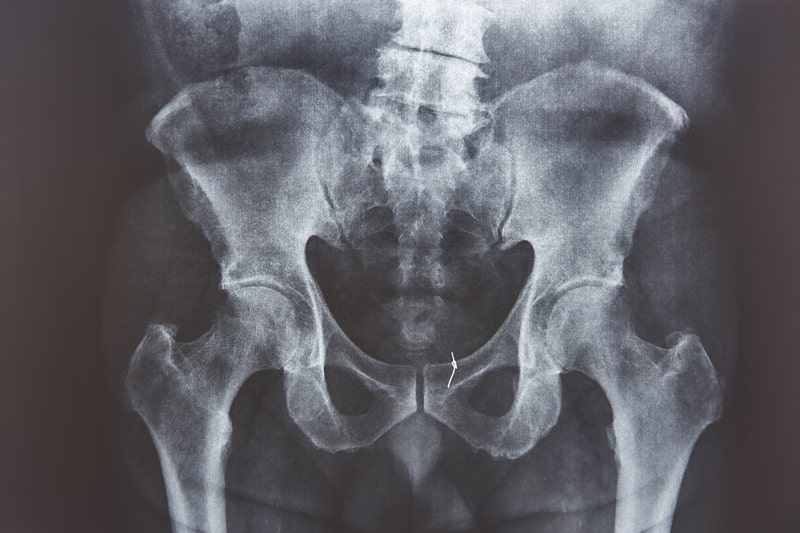

A Síndrome da Dor Pélvica Crônica (SDPC) representa uma condição caracterizada por dor persistente ou desconforto localizados em qualquer ponto que se estenda desde o umbigo até a região da coxa.

Embora a síndrome da dor pélvica crônica seja frequentemente associada à região dos órgãos reprodutivos femininos, ela pode ocorrer em todos os sexos e ter origens diversas.

Esta dor pode ser indicativa de uma infecção ou derivar de condições relacionadas aos ossos pélvicos ou órgãos internos não reprodutivos.

Trata-se de um distúrbio multifatorial, no qual a origem da dor pode estar associada a sistemas como o uroginecológico, gastrointestinal, musculoesquelético, pélvico e nervoso.